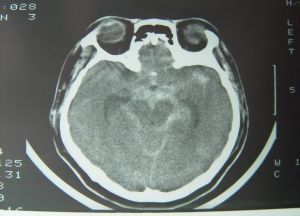

動脈瘤再破裂

是血管內栓塞術的嚴重併發症,因血壓急劇波動、術中機械刺激、術後抗凝治療凝血機制改變引起的。瘤體的破裂與死亡率隨著年齡的增加而上升。病人可突然出現精神緊張、痛苦表情、躁動、劇烈頭痛、不同程度的意識障礙、小便失禁。急查CT示蛛網膜下腔出血,腰穿可見血性腦脊液。護理病人隨時一定要細心觀察,及時發現並通知醫生及時處理。術後入神經外科ICU仔細觀察病人的意識狀態、瞳孔變化、肢體活動情況、生命體徵特別是血壓和呼吸改變。對血壓高者控制性降低,將血壓降至16/1lKpa左右。對清醒病人,指導其絕對臥床48~72h,48h內勿劇烈晃動頭部,保持情緒穩定及大便通暢。

腦積水

是動脈瘤術後最常見的併發症。急性腦積水在手術同時行腦室外引流即能解決,而慢性腦積水需行手術分流。